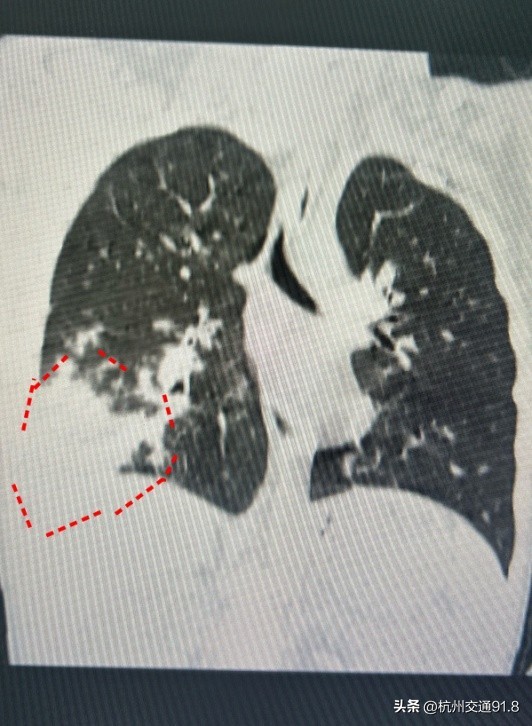

几天前,7岁男孩悠悠(化名)久咳不愈发生了气喘来到了儿科诊室。接诊的郑绪阳询问后得知,原来在三个多星期前,悠悠发过三天高烧,当时爸爸妈妈跟以前一样,给他服用了家里常备的抗生素和退烧药。三天后悠悠退烧了,退烧后却一直咳嗽,越咳越厉害,这才来到医院。经过胸部CT检查,发现他的左肺已经白掉了一大块。之后的化验结果证实,悠悠患上了支原体肺炎,马上被收治入院。所幸,悠悠的恢复能力较强,在住院治疗后,病情逐渐好转。

像悠悠这样没有持续高烧,做了血常规也没有明显改变,怎么会患上严重的支原体肺炎?郑绪阳说,现在的肺炎症状不一定典型,很多支原体肺炎单纯从症状上来和普通感冒较为相似。前期可能表现为单纯高热,或单纯咳嗽,血常规正常,胸片表现为单片或者间质性肺炎,进行病原学检测才能明确,非常隐匿,容易漏诊。